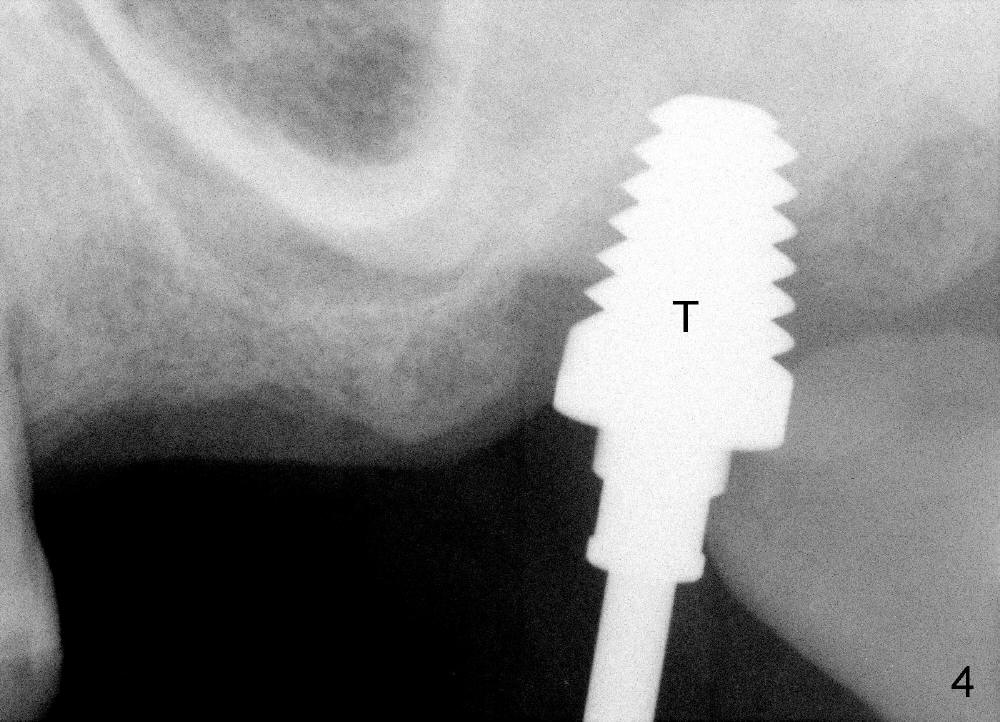

In fact, a tapered tap of 8x14 mm was used (Fig.4 T) before the implant of equivalent size was placed (Fig.5: I). The patient and the implant are doing fine after surgery. No bone loss is noted 4 years 4 months post cementation (Fig.6).